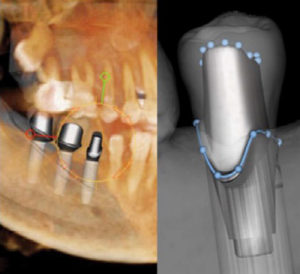

The data from CBCT scans led to a level of surgical predictability that I could not achieve with 2D imaging alone. Scans showed the buccal aspect of the teeth would have protruded too far into the cheek and the lip for the routine crown and bridge I had originally intended to pursue. With the i-CAT scan, surgical guides were created for placement of the implants. I worked with the laboratory to create custom castings and implant framework that protruded more lingually for a better aesthetic and clinical outcome. I facilitated a removable appliance that functioned like much of the tissue he lost after the oral surgery.

The patient came to me for solutions, and I was able to devise a reconstruction plan that took his individual and challenging needs into consideration. With information from the 3D scans, the spacing is so good, the patient has experienced no residual problems. After treatment, he was able to chew on that side and looked almost the same as he did prior to the surgery.